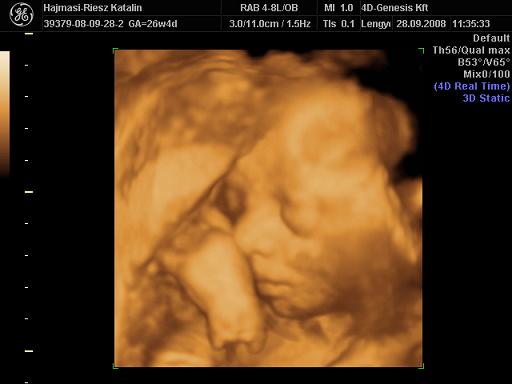

Lányok, kit hoztam?? :lol:

Kép

Mit mondjak, szuper élmény volt, nagyjából egy órát töltöttünk bent, nem volt utánunk senki :wink: Martin szép nagyot nőtt, 940 g, azt mondták, ha ilyen ütemben nő, kb 3500 g lesz mire születik! Ezzel abszolút ki is egyeznék :D Mindene rendben van, mintaszerű,csodálatos baba, édesen rángatta a köldökzsinórt megint, egyszer meg spontán bekapta a lábát :lol: Jó nagy tappancsunk van, most 5 cm-es :wink: Készült 58 kép CD-re, meg DVD és egy papír kép.

Szóval,nagyon-nagyon elégedett vagyok és abszolút pozitív volt az élmény, a szakszerűség és a törődés!!! :D

Mi elmentünk ebédelni, megünnepelni a végre sikeres 4D-t :oops:

Kata! Gyönyörű Martin baba! Szerintem már most hasonlít rád!!!!

Köszi Hanna :wink: Mi is azt lestük, hogy látszik-e már, kire hasonlít :oops: Az biztos, hogy a fejformája az enyémre üt, én voltam ilyen kis golyófejű :oops: :lol: De hogy ez a tündéri orrocska kitől jön, azt még nem tudom :lol: